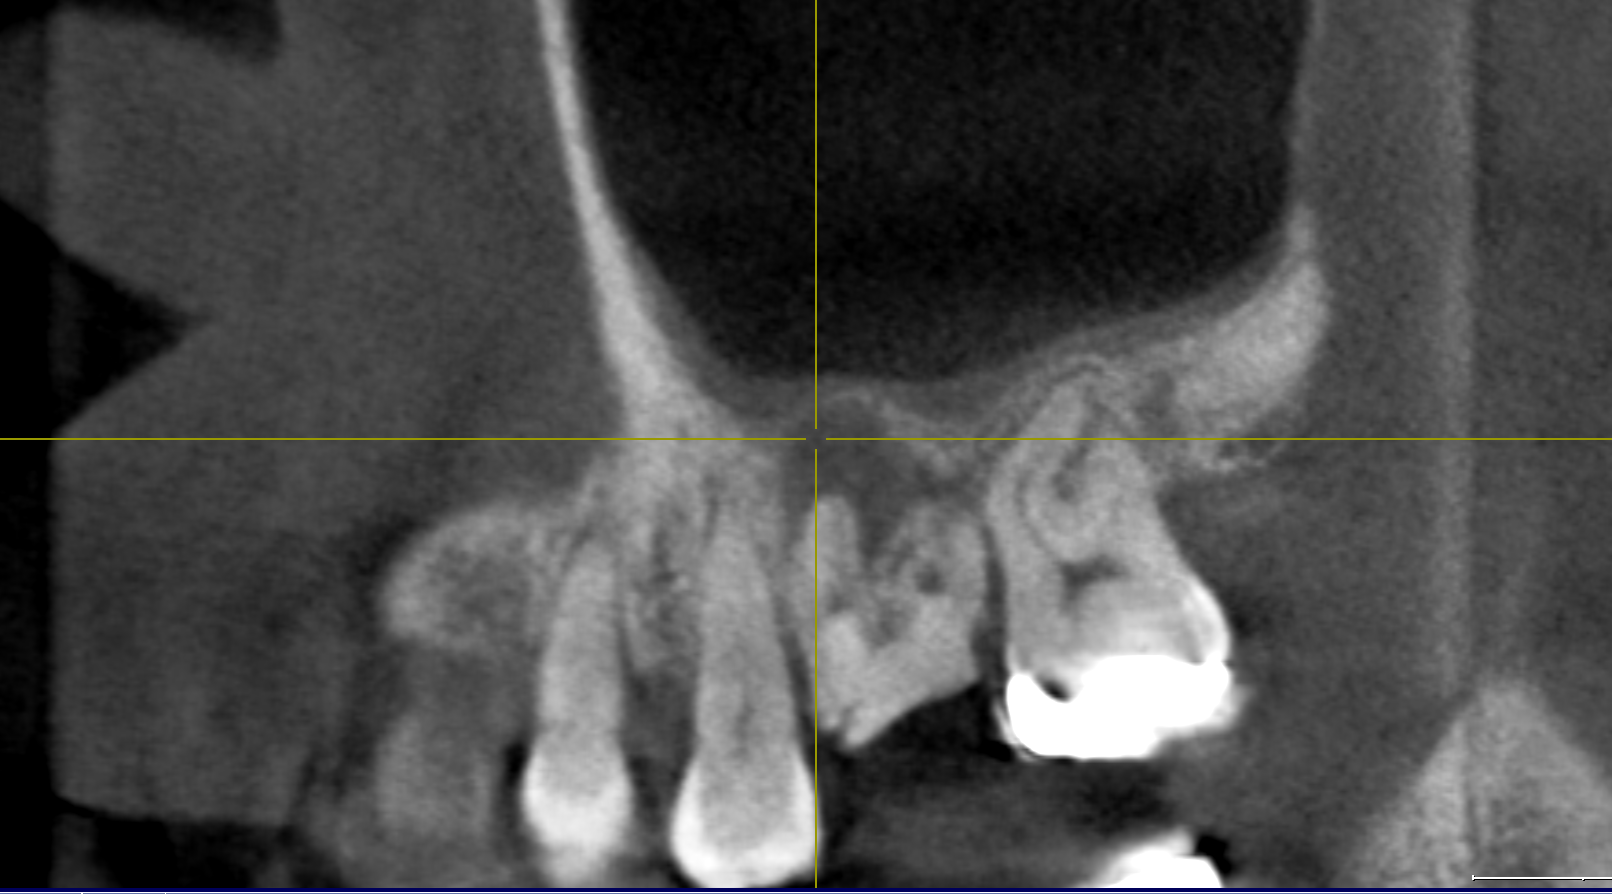

CT:重症の虫歯が根管を超え鼻の部屋に入っていました。鼻から変な汁もでる状況。皆さん歯科ドックではここまでわかります。必ず精密検査をお勧めします。骨にも穴が開いている。。。。

シンプルにいくなら抜歯。かなと。これはもし残すなら精密根管治療が必要ですがCTを見ると根管が狭窄(詰まっている)して器具が貫通できない可能性が高いのです。

やはり膿が!!感染源が。そして肝心の根管がやはりCTで見た通り狭窄。通らない。

今日ダメだったらやめましょう。そう伝えCTを術前に撮影。

鼻の部屋の病気が引いていました!!嬉しい。治癒傾向は間違いがない。ただ治癒だけではだめだ。根治だと自分に言い聞かせ昼休みを使ってゆっくり丁寧にマイクロスコープで根管を探りました。

根尖見えますね。根管を綺麗にして。次回根充(MTA)予定です。時間がかかったけど本当に良かったです。お付き合いいただいたMさんに感謝!!